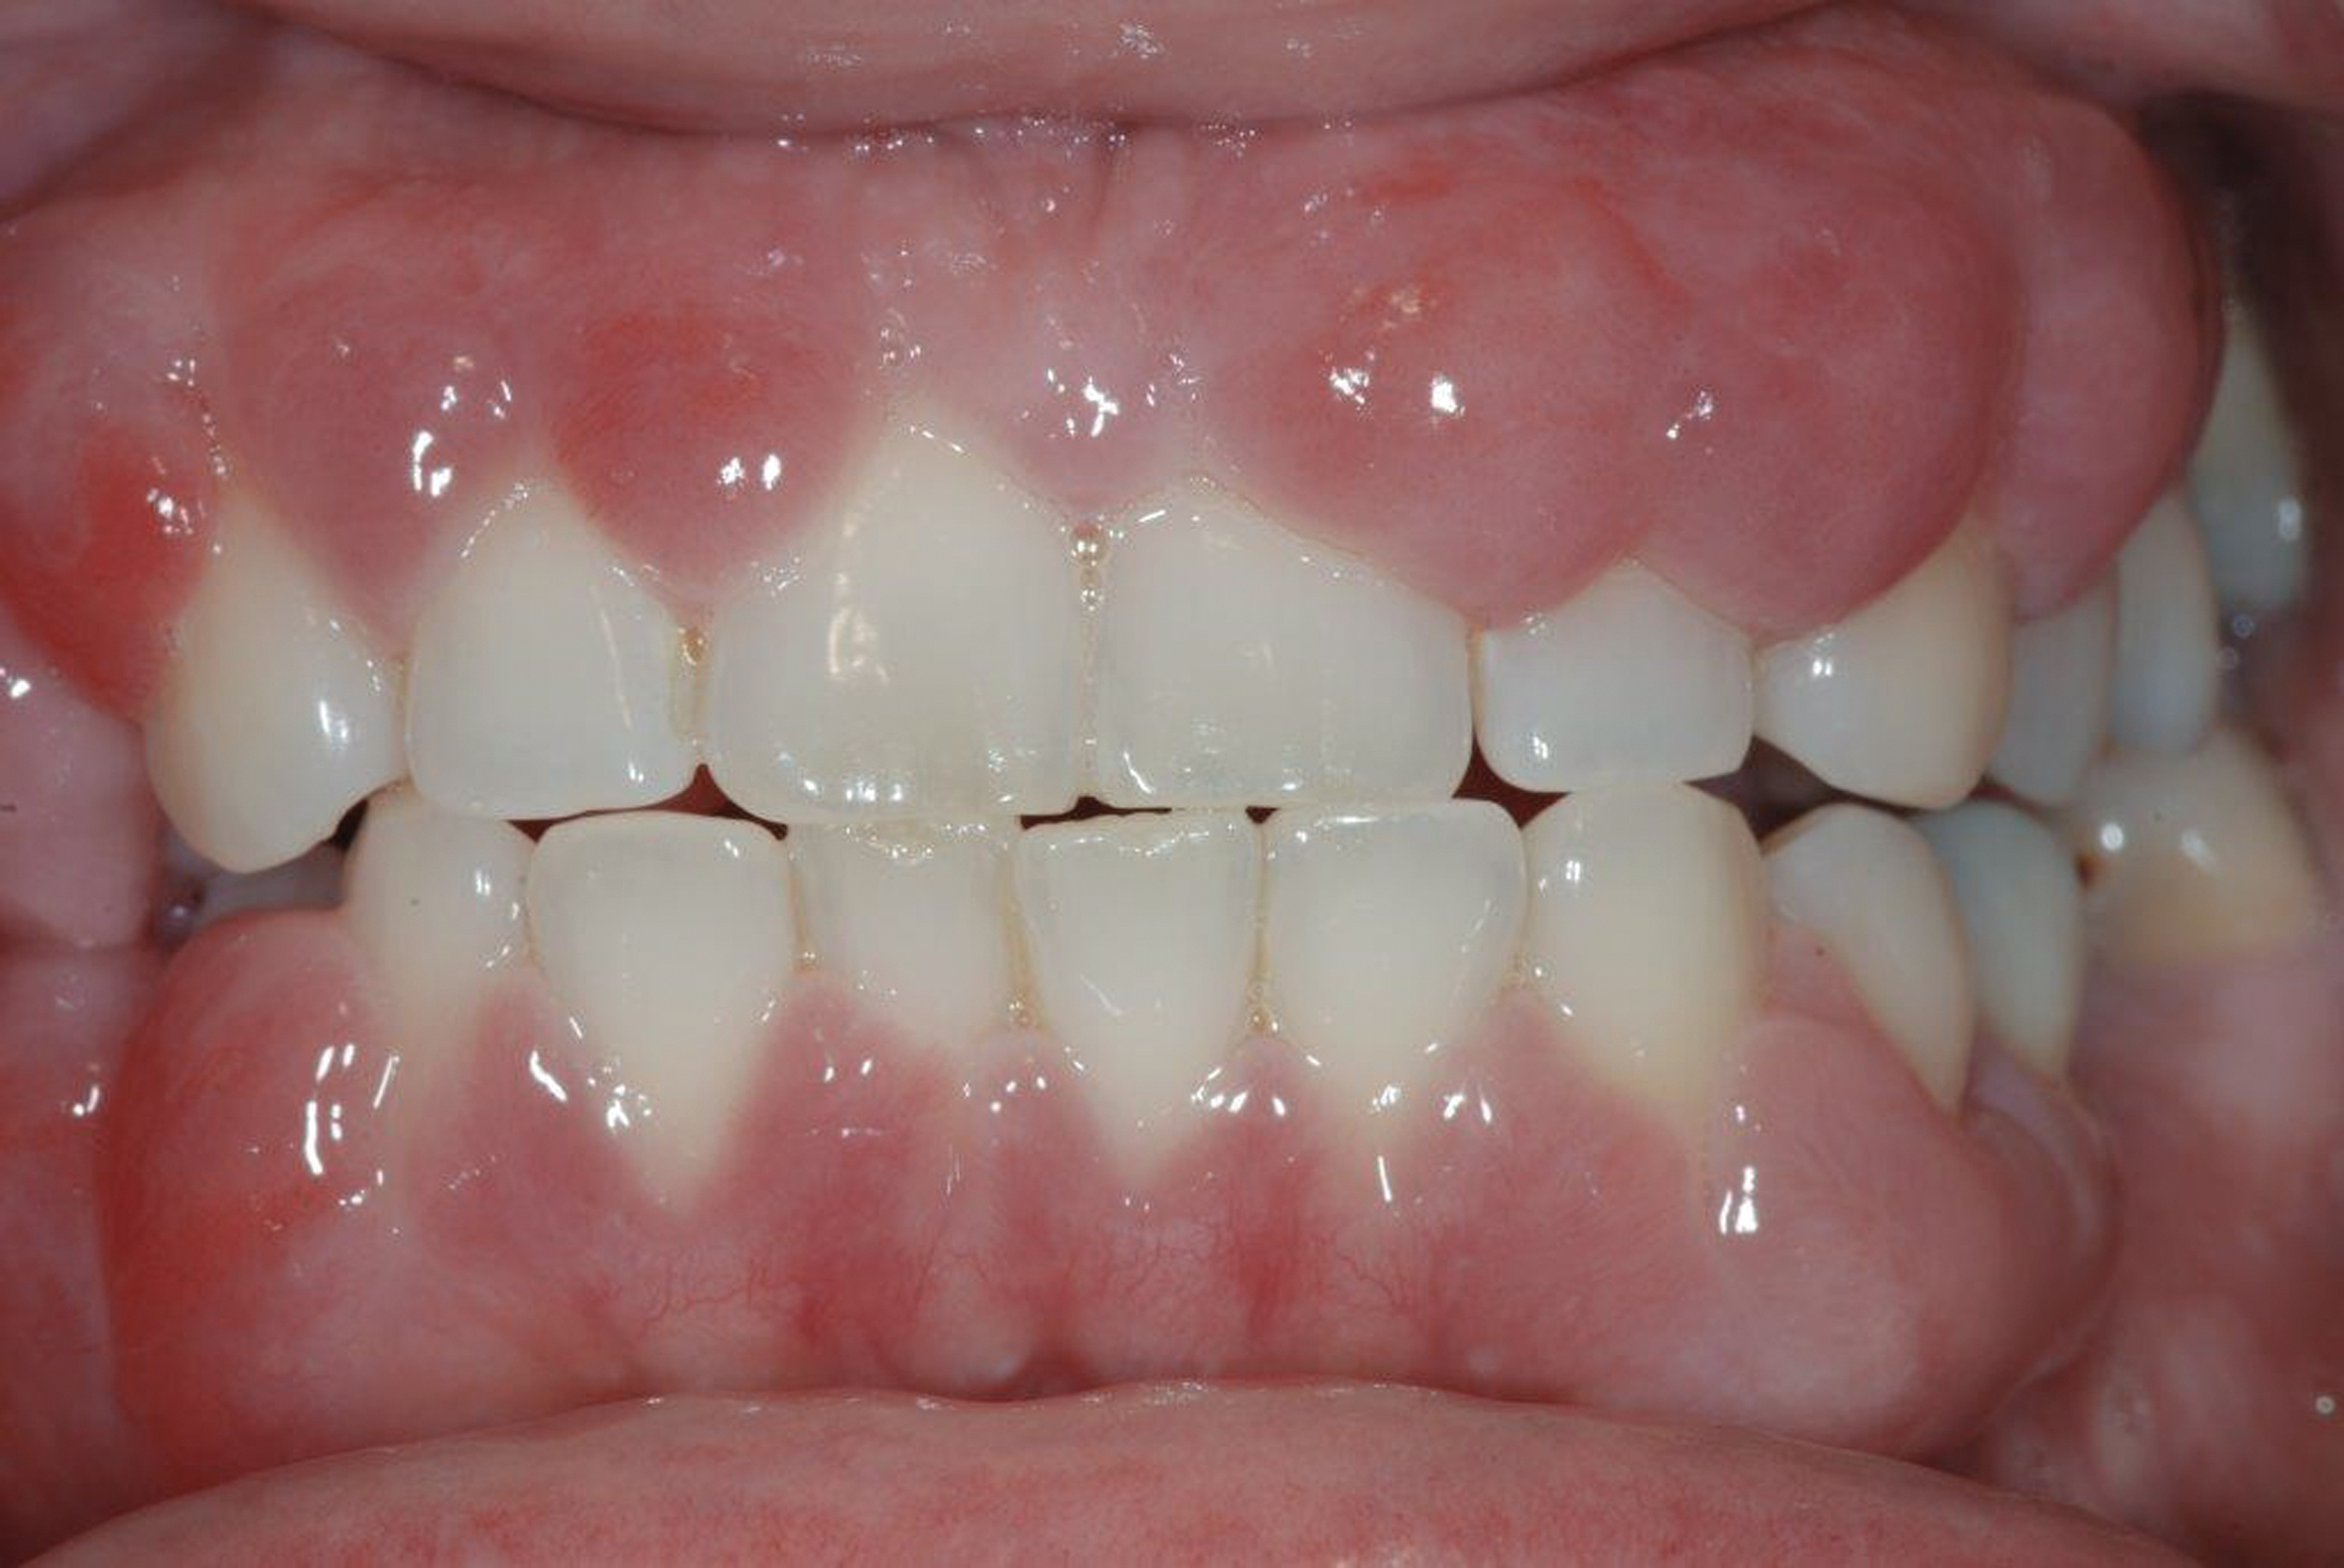

The authors consider GS and STS as two esthetic smile alterations that often coexist and have similar or coincident etio-anatomo–pathological origin and need to be diagnosed simultaneously with identical guidelines. Some of the causes of GS—including deep bite and overeruption and compensatory eruption (wear/erosion) in teeth, as well as gingival hyperplasia and altered active/passive eruption in gingiva—can also be identified in STS; however, vice versa is not the case. The aim of this article is to propose a classification of such adult patients and briefly describe a diagnostic process to use with this classification, and to identify a correct treatment plan that can lead to a successful treatment outcome (Figure 2).

Fig 2. Resolution of gummy smile after treatment in patient shown in Fig 1.

Figure 2